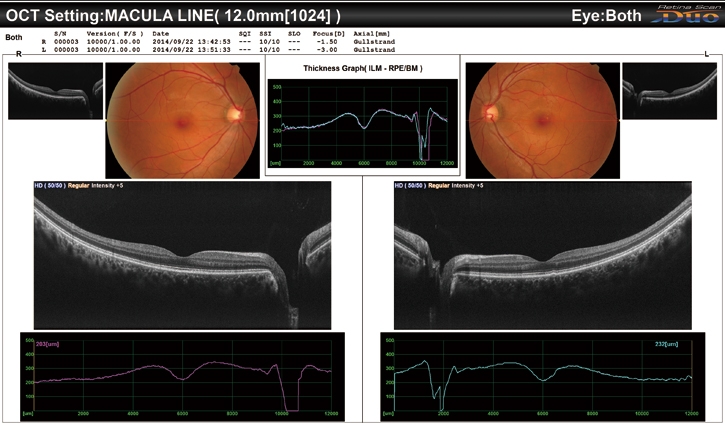

OCT成像時,平均提供多達50張圖像進行疊加,可根據實際情況,選擇超精細、精細和普通OCT敏感度。RS-330內置12兆像素CCD攝像頭,能夠提供高質量眼底圖像。

廣域掃描(12 x 9 mm)/ 廣域標準化數據庫(9 x 9 mm)

利用RS-330,可在黃斑中心進行12 x 9 mm廣域成像。9 x 9 mm標準化數據庫提供了彩色編碼圖,該圖說明了在正常眼睛中,患者的黃斑厚度分布范圍。